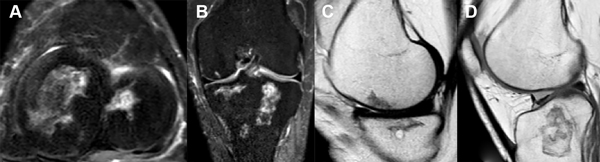

Realizamos resonancia magnética de control a los veinticuatro meses. Tanto en los cortes axiales, sagitales como coronales de la rodilla derecha (fig. 9) como de la rodilla izquierda (fig. 10) no evidenciamos grandes cambios en relación a una posible mejoría, tampoco una probable progresión de la enfermedad en relación con las múltiples imágenes compatibles con infartos óseos que ya veíamos en la RM preoperatoria.

Figura 9: RM rodilla derecha. A) Corte axial. B) Corte coronal. C y D) Cortes sagitales. Focos osteonecróticos, tanto en fémur como tibia, ya conocidos en imágenes preoperatorias, sin grandes cambios evolutivos.

Figura 10: RM rodilla izquierda. A) Corte axial. B) Corte coronal. C y D) Cortes sagitales. Múltiples infartos óseos difusos ya diagnosticados en imágenes preoperatorias, sin grandes cambios evolutivos.